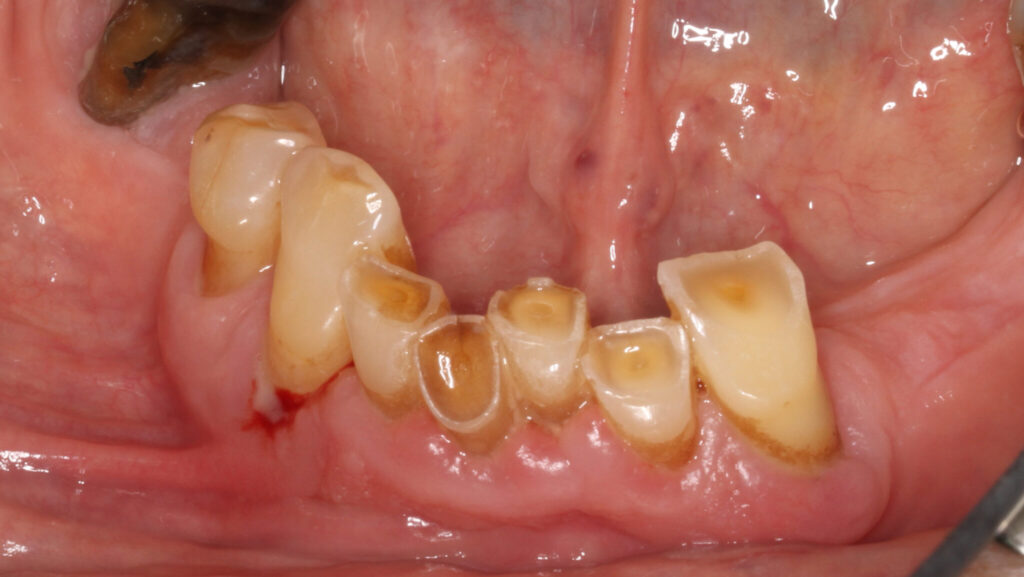

A 65-year-old woman comes to the office with the chief complaint of worn-down teeth, missing teeth, tooth sensitivity, especially on maxillary teeth and TMJ pain. Her past medical history was reviewed and was significant for asthma, insomnia, hypercholesterolemia, hypothyroidism, and anxiety disorder. She denied any sleep disturbances. Her medications included salbutamol, ezetimibe, quetiapine, and levothyroxine. She referred to being allergic to dust and shellfish and sensitive to propofol. She had a right mastectomy in 2014 due to breast cancer. No chemotherapy or radiation was done. Her diet was considered normal, and she denied any consumption of acidic drinks and denied any history of regurgitation. She denied any parafunctional habits during the day. She was using a maxillary transitional partial denture since she had lost some of her teeth due to fracture and caries. No other problems were evidenced. Intraoral exam showed moderate attrition lesions of posterior teeth, porcelain fused to metal crowns on teeth 46 and 47 had the porcelain portion worn down, exposing the metal substructure. Missing teeth included teeth 14,15,16,18,24,28, 36,38,48. Palatal surfaces of maxillary anterior teeth also appeared worn down. An abfraction lesion was found on tooth 23. No carious lesions were found in any of her teeth. Composite restorations on mandibular anterior teeth were chipped or were missing (Figs. 6-11) She also presented with limited mouth opening: 35 mm interincisal distance at maximum opening. There was bilateral pain on palpation of preauricular areas. Her pain was the worst early in the morning which suggested night parafunction. No crepitus, or joint clicking were found.

Fig. 6